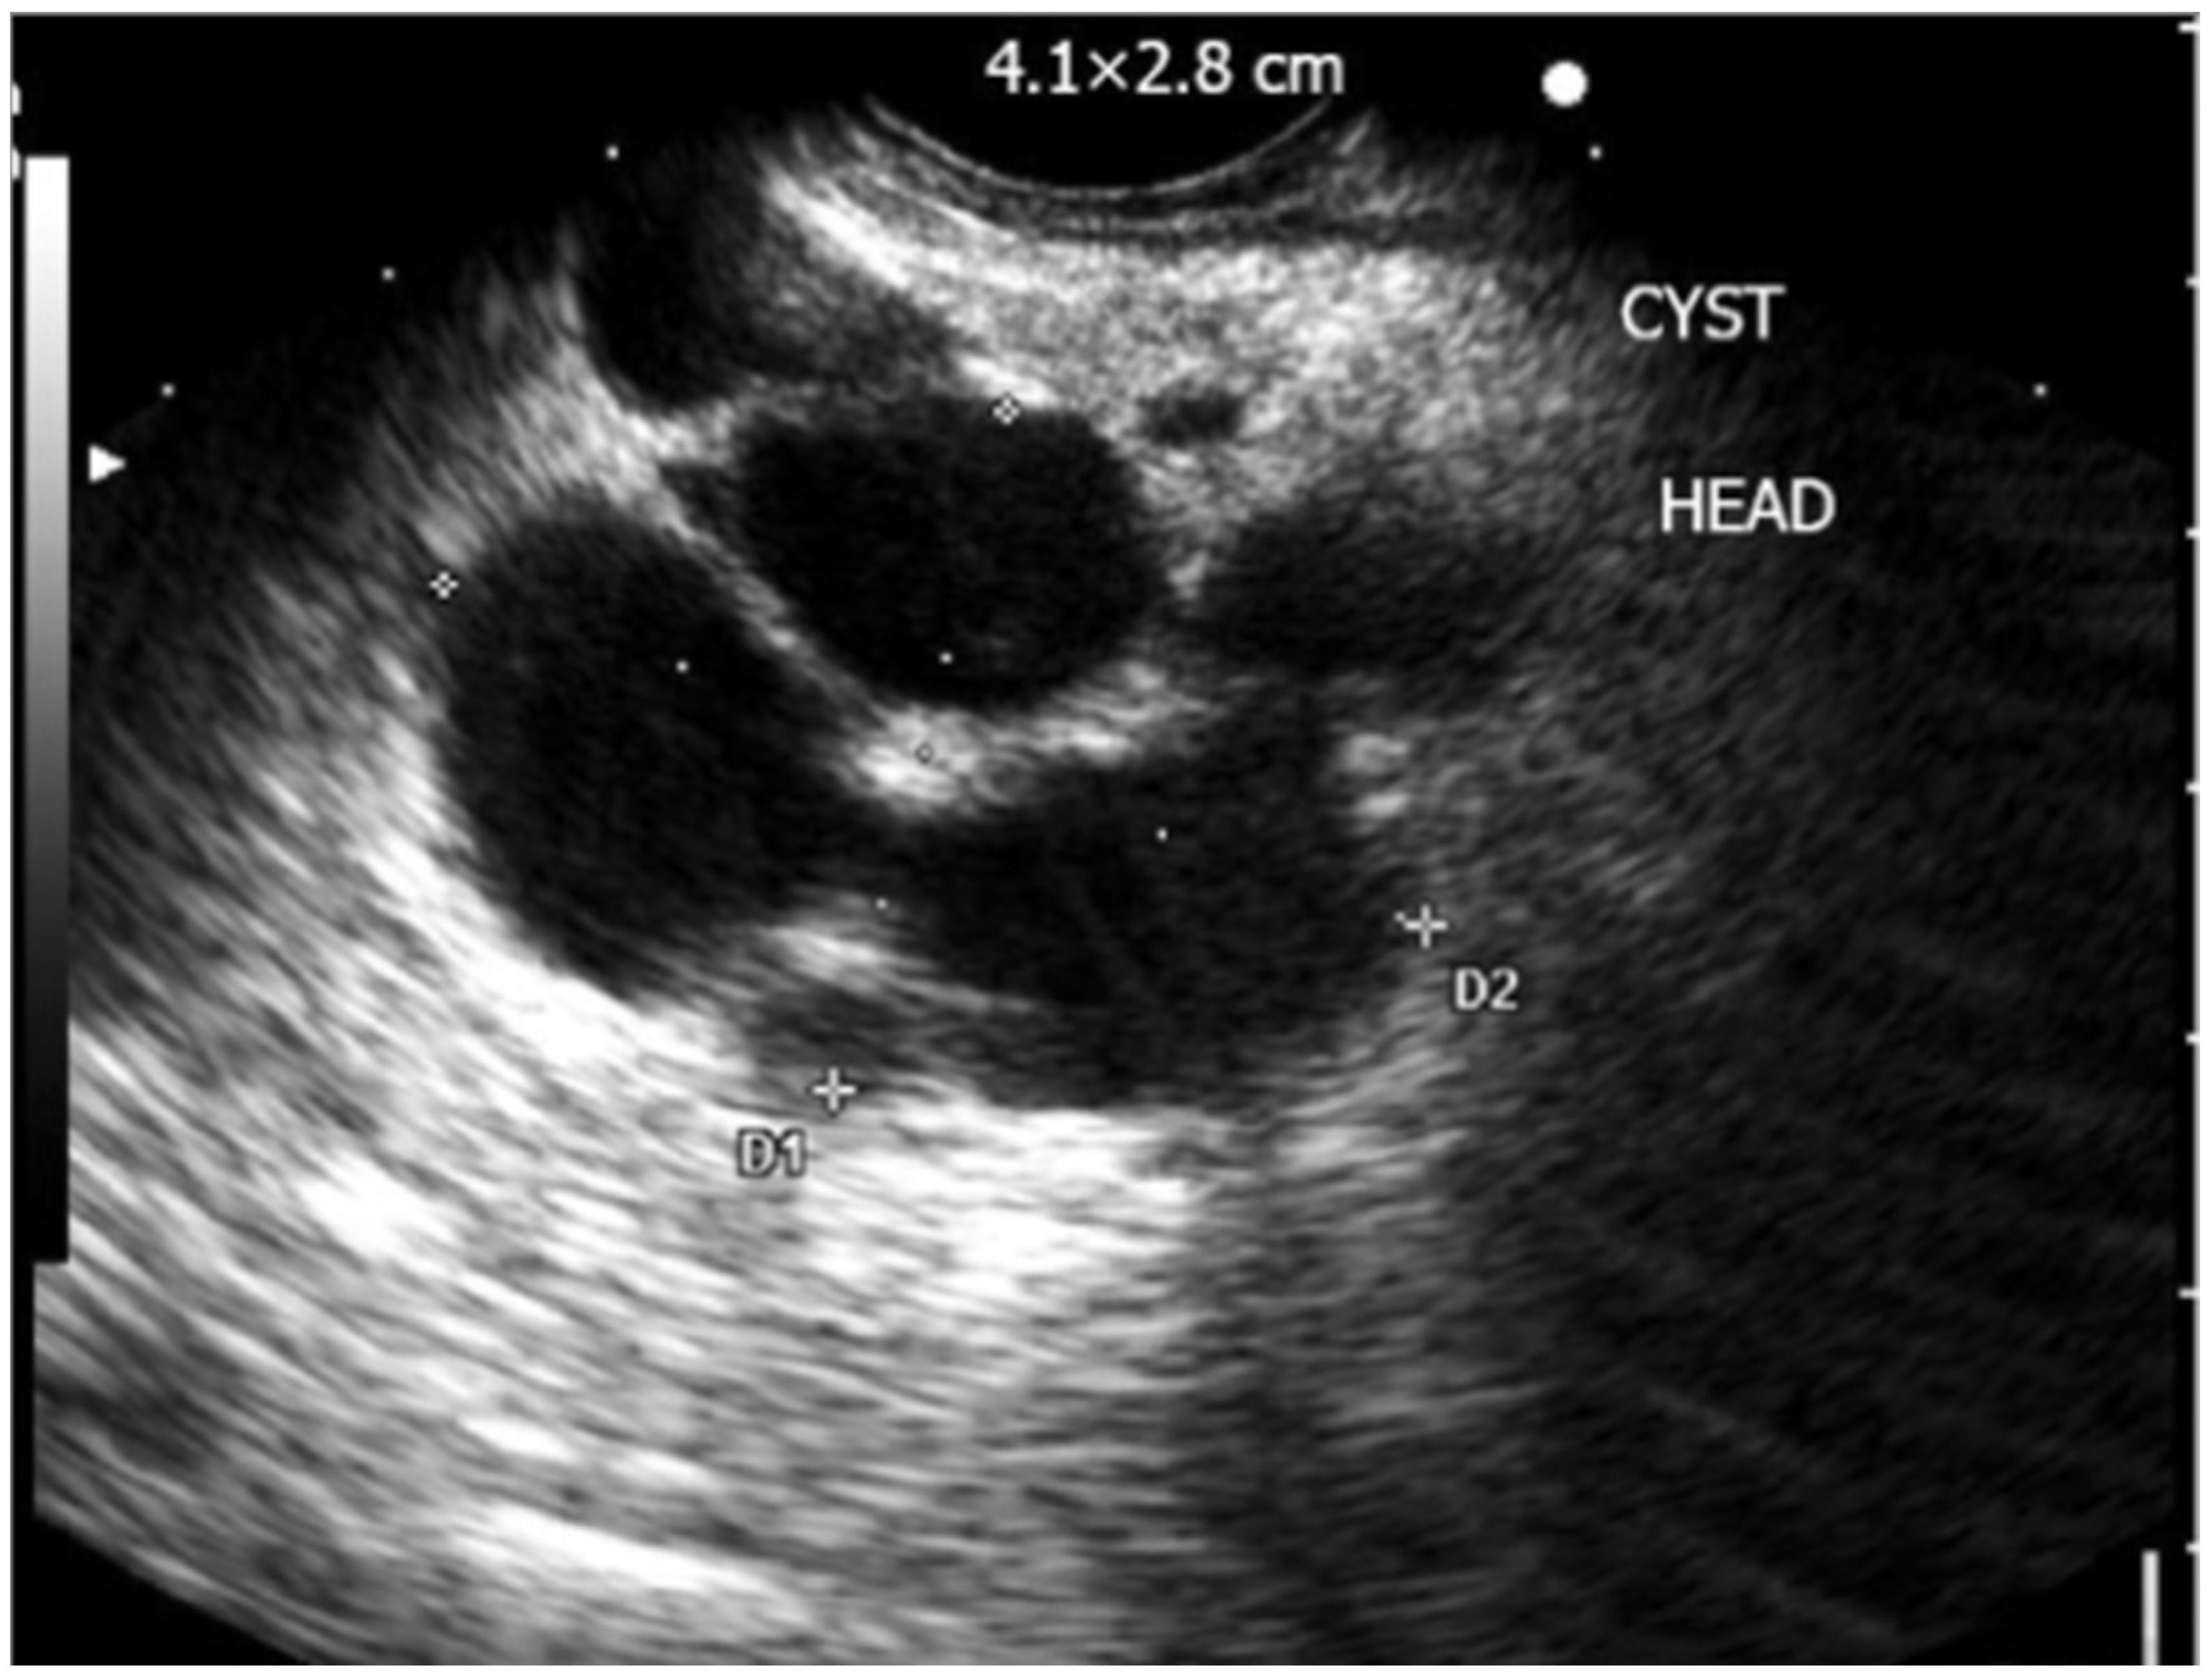

4. Miniature Probe Endoscopic Ultrasound